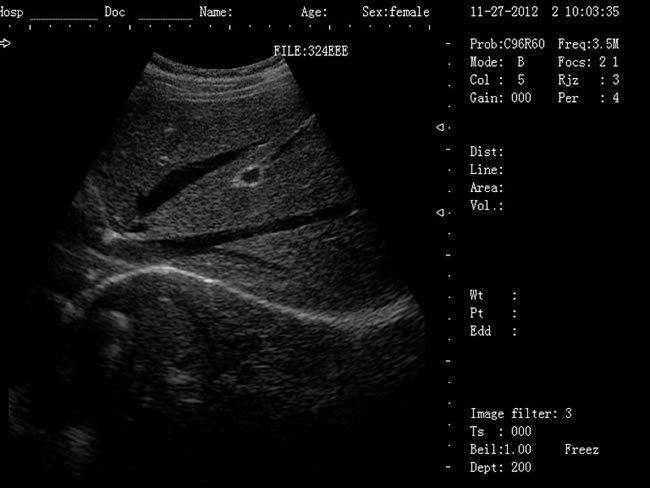

| 老式的b超機黑白要多少錢?已被新型B超機所取代! |

老式的b超機黑白要多少錢?老式的B超機是CRT顯示器,CRT顯示器學名為“陰極射線顯像管”,是一種使用陰極射線管的顯示器?,F(xiàn)在科技進步,已經慢慢被新型顯示器所取代。老式的黑白b超機CRT顯示器主要有五部分組成:電子槍,偏轉線圈,蔭罩,高壓石墨電極和熒光粉涂層及玻璃外殼。感謝大家對我司CRT顯示器相關產品長久以來的支持與厚愛,該系列機型因順應市場的需求,已經無法滿足客戶的生產需求。該系列機型正式停產,后期不再供應該型號的儀器。給廣大的新老客戶造成的不便敬請諒解。應廣大用戶的需要,CRT相關產品的售后服務依然支持,同時保留儀器后期的維修部件。

徐州大為DW-500筆記本b超機 1、DW-500產品特點: (1)DW-500是一款高陣元、高清晰度、多功能的筆記本式超聲診斷儀。 (2)它的小巧輕便,圖像清晰,操作方便、續(xù)航能力強,在城市、鄉(xiāng)鎮(zhèn)、戶外等,各種環(huán)境下會診的超強優(yōu)越性。 (3)多種充電方式更保證了在不同環(huán)境下檢查會診。 2、DW-500新增3大看點: (1)5-7小時超長待機時間 (2)12.1英寸LED液晶顯示器 (3)全數(shù)字96陣元 3、一流的數(shù)字成像技術,圖像更清晰 (1)DBF全數(shù)字波束形成 (2)DRF實時逐點動態(tài)接受聚焦 (3)DRA實時動態(tài)聲速變跡 (4)THI組織諧波成像 (5)RDA實時動態(tài)孔徑成像 (6)DFS數(shù)控動態(tài)頻率掃描 (7)RDF實時動態(tài)濾波 4、靈活方便的操作系統(tǒng) (1)12.1英寸LED液晶顯示器 (2)背光硅膠鍵盤,更舒適耐磨,暗室中使用不再煩惱 (3)智能化菜單,人機對話輕松快捷 (4)顯示穿刺引導線,角度和位置可調 (5)多倍率顯示,病變診斷更準確 (6)外接USB存儲,圖像上傳更方便 (7)大容量的電影回放,圖像自動循環(huán)演示 (8)豐富的測量功能:距離,周長,面積,體積,產科測量表,心臟軟件包等 (9)顯示模式:B、B+B、4B、B+M、M (10)電影回放:≥256幀,可連續(xù)回放或逐幅查看 (11)具有穿刺引導功能,穿刺線位置可調節(jié) (12)具有碎石定位,動態(tài)靶區(qū)跟蹤功能 (13)主機尺寸:330x289x70mm(長x寬x高);

(14)凈重:4.7kg